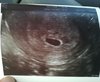

Troche źle napisałam. Pęcherzyk miał 1 cm :) serduszka jeszcze nie było słychać ale ciałko żółte jest widoczne więc wszystko jest ok :) ostatni okres miałam 2 października.

• 9903739_IMG_20171106_134829.jpg

27,6 KB · Wyświetleń: 85